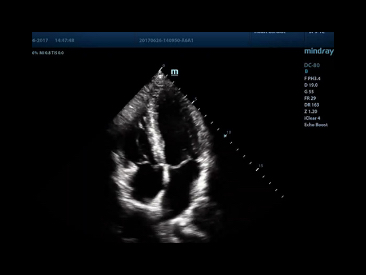

MINDRAY DC 80 X INSIGHT ULTRASOUND

MINDRAY DC 80 X INSIGHT ULTRASOUND

Mindray DC 60 Echo Ultrasound machine

Mindray DC 60 Echo Ultrasound machine